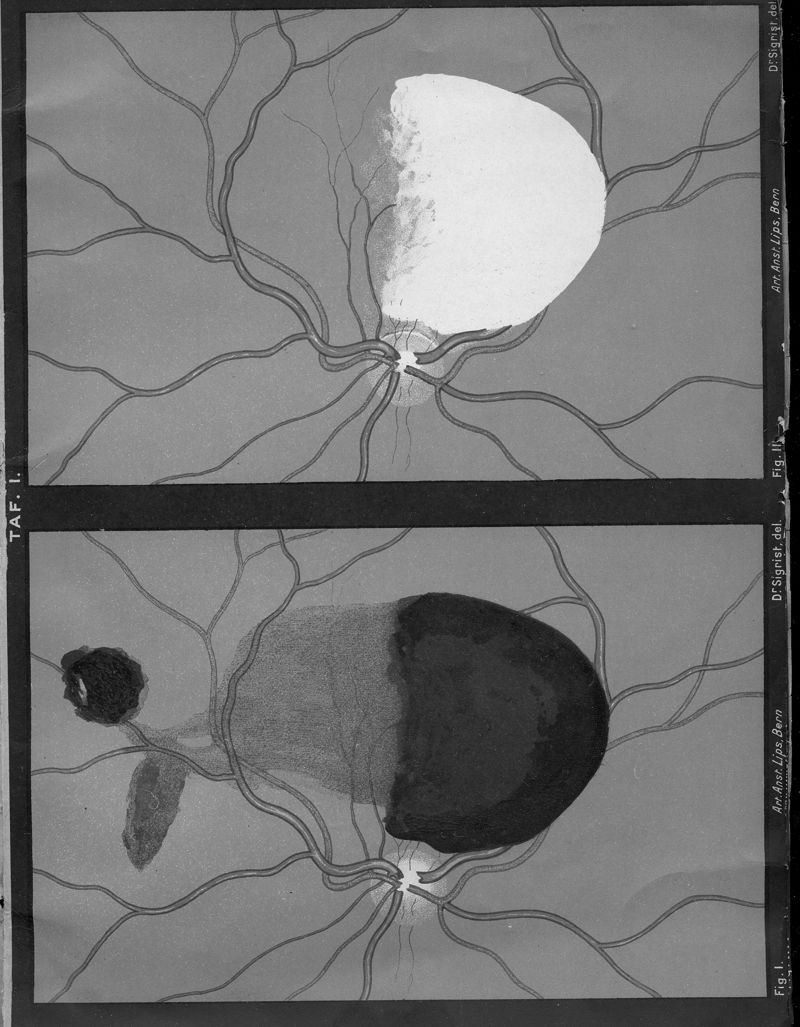

SIEGRIST, A.

In : Mitteilungen aus kliniken und medicinischen Instituten der Schweiz,

1895, Vol. 3, pp. 545-82

SIEGRIST, A.

In : Mitteilungen aus kliniken und medicinischen Instituten der Schweiz,

1895, Vol. 3, pp. 545-82